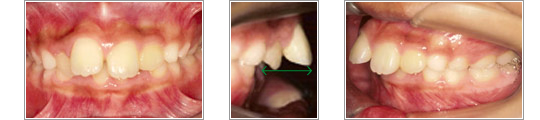

写真左:咬み合わせが深く、下の前歯がほとんど見えません。上と下の前歯にでこぼこがあります。

写真中、右:上の前歯と下の前歯の距離がかなりあります。

この症例は上の顎の大きさは正常で下の顎が小さく、相対的に出っ歯にみえます。

第1期治療の最大の目標は、下の顎の成長をうまく引き出すことです。上の前歯4箇所と奥歯2箇所に固定式の装置を使用し、上の前歯をまっすぐに並べました。その後、下の顎の前方成長を促進する取り外し式の装置を使用しました。